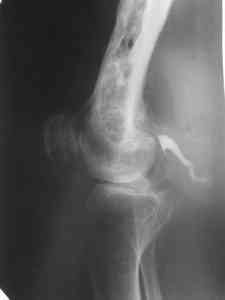

Больной 53 лет, страдает остеомиелитом с 1975г.,после закрытого перелома с/3 бедра и интрамедулярного остеосинтеза. Выполнено более 30 операций без особого эффекта. Какой комплекс операций может помочь больному? Больной, 1954 г.р.Клинический диагноз: хронический травматический тотальный остеомиелит левой бедренной кости, секвестрально - свищевая форма, часторецидивирующее течение. Ложный сустав шейки левой бедренной кости. Укорочение левого бедра 10 см. Контрактура коленного сустава. Жалобы: боли в области левого бедра, коленного сустава, нарушение функции левой ноги, наличие свища с гнойным отделяемым в левой подколенной области, свища в области в\з бедра. Анамнез: в 1975 г. получил закрытый перелом с\з левой бедренной кости. Оперирован в районной больнице - выполнена открытая репозиция, интрамедуллярный остеосинтез. Осложнение - нагноение раны с исходом в остеомиелит бедренной кости. В последующий годы - трижды патологический перелом бедра. Оперирован за эти годы около 30 раз по поводу обострения остеомиелита. За последние 5 лет обострения ежегодно по 2- 3 раза в год. Динамика отрицательная. Рентгенологически - тотальное поражение бедренной кости. Объективно: передвигается при помощи костылей с дозированной нагрузкой на левую ногу. При нагрузке на левую ногу - стопа в положении эквинуса, опора на передний отдел стопы. Выражена атрофия мышц левого бедра, голени. На всем протяжении бедра - множественные рубцы после оперативных вмешательств. В в\з бедра по наружной поверхности - грубый втянутый рубец с вялогранулирующей раной на дне его. Отделяемого нет. В области подколенной ямки - свищ с гнойным отделяемым серо - зелоноватого цвета без запаха. Укорочение бедра 10 см. Движения в тазобедренном суставе активно 180 - 160 град., пассивно 180 - 90 град. В коленном уставе 178 - 110 град. Чувствительных расстройств конечности нет.Лабораторные данные: Общ. ан. крови: 20.04.07. Нв-135 г\л, Er 4.22 млн., Le-9.7 тыс, Эоз. 4%, Пал.-5 %, Сегм.-60 %, Лимф. - 25 %, Моноц.-6 %, СОЭ 51мм\час.Биохимический ан. крови от 20.04.07г. Белок -77 г/л, сахар крови 5.38 ммоль/л., билирубин 10.2 мкмоль/л. Тимоловая проба 2.5 ед.пом. Ан.мочи от 20.04.07. : отн. плотность1026, белок - отр, сахар -отр, ЭКГ от 22.02.07 : отклонение ЭОС влево.. Неполная блокада правой ножки пучка Гиса. Флюорография от 28.12.2006 года № 038 - без патологии. R - графия : грубая деформация и склерозирование бедренной кости от проксимального до дистального метафиза , множество очагов просветления в области дистального метаэпифиза, н\з бедра. МРТ коленного сустава, н\з бедра от 21.04.2007г. - картина хронического остемиелита левой бедренной кости. Имеется полость деструкции в дистальном метадиафизе протяженностью до 12 см. Полость имеет неоднородное содержимое за счет гноя, грануляций, секвестров, сообщается со свищевым ходом, идущим в подколенную ямку.